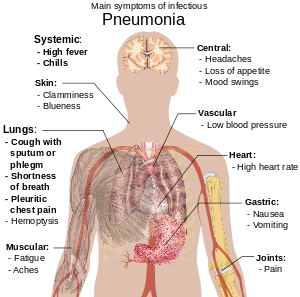

People with infectious pneumonia often have a productive cough, fever accompanied by shaking chills, shortness of breath, sharp or stabbing chest pain during deep breaths, and an increased respiratory rate. In the elderly, confusion may be the most prominent sign. The typical signs and symptoms in children under five are fever, cough, and fast or difficult breathing.

Fever is not very specific, as it occurs in many other common illnesses, and may be absent in those with severe disease or malnutrition. In addition, a cough is frequently absent in children less than 2 months old. More severe signs and symptoms may include: blue-tinged skin, decreased thirst, convulsions, persistent vomiting, extremes of temperature, or a decreased level of consciousness.

Bacterial and viral cases of pneumonia usually present with similar symptoms. Some causes are associated with classic, but non-specific, clinical characteristics. Pneumonia caused by Legionella may occur with abdominal pain, diarrhea, or confusion, while pneumonia caused by Streptococcus pneumoniae is associated with rusty colored sputum, and pneumonia caused by Klebsiella may have bloody sputum often described as "currant jelly". Bloody sputum (known as hemoptysis) may also occur with tuberculosis, Gram-negative pneumonia, and lung abscesses as well as more commonly with acute bronchitis. Mycoplasma pneumonia may occur in association with swelling of the lymph nodes in the neck, joint pain, or a middle ear infection. Viral pneumonia presents more commonly with wheezing than does bacterial pneumonia.